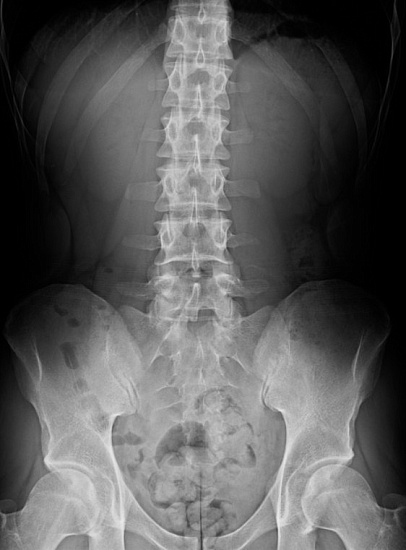

Рентгенография пояснично-крестцового отдела позвоночника Рентгенография пояснично-крестцового отдела позвоночника

Рентгенография пояснично-крестцового отдела позвоночника

Рентгенография пояснично-крестцового отдела позвоночника – важный метод скринингового исследования, который позволяет оценить состояние пояснично-крестцового отдела позвоночника.

Диагностическая услуга выполняется в двух проекциях.